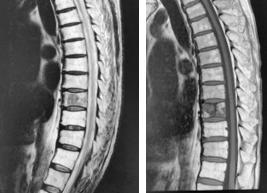

(左)術前MRI 第4/5腰椎に椎間板ヘルニアを認めます。

(中)内視鏡下(MED)にヘルニアを摘出しました。

(右)術後MRI 第4/5腰椎の椎間板ヘルニアが消失しています。